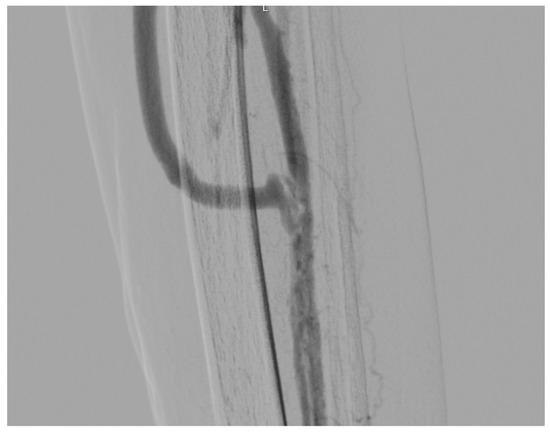

Figure 4 shows the final angiographic result after PTA.

Figure 4.

Angiography frame of the distal anastomosis on the peroneal artery.